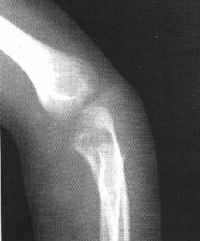

影像学表现]

儿童的肱骨外髁骨骺骨折X线上可见肱骨外髁骨骺或骨骺的骨折部分与肱骨远端分离明显,往往连同从干骺端撕脱的小骨片一起向外有反转变位。这是由于附着在外髁的伸肌健的牵拉所致。部分患者同时合并有尺骨鹰嘴骨折

X线照片显示肱骨小头的骨折线多超过化骨核的1/2,或不通过小头化骨核,而通过肱骨小头与滑车间沟的软骨在干骺端处有一骨折线。骨折块可向外侧移位。骨折脱位型X线片,正位片显示骨折块连同尺桡骨可向桡侧或尺侧移位,侧位片显示可向后侧移位,偶可见向前移位者。肱骨外髁骨折在X线片上表现为多种多样,在同一骨折类型中表现也常不一。